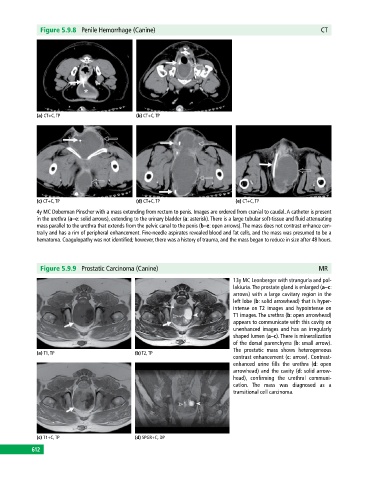

Figure 5.9.8 Penile Hemorrhage (Canine) CT

(a) CT+C, TP (b) CT+C, TP

(c) CT+C, TP (d) CT+C, TP (e) CT+C, TP

4y MC Doberman Pinscher with a mass extending from rectum to penis. Images are ordered from cranial to caudal. A catheter is present

in the urethra (a–e: solid arrows), extending to the urinary bladder (a: asterisk). There is a large tubular soft‐tissue and fluid attenuating

mass parallel to the urethra that extends from the pelvic canal to the penis (b–e: open arrows). The mass does not contrast enhance cen

trally and has a rim of peripheral enhancement. Fine‐needle aspirates revealed blood and fat cells, and the mass was presumed to be a

hematoma. Coagulopathy was not identified; however, there was a history of trauma, and the mass began to reduce in size after 48 hours.